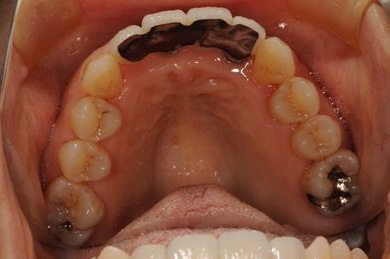

| 性別/年齢 | 女性 / 52歳 | ||||||||||||||||||||||||||||||||

| 主訴 | 歯周病で歯の位置がずれてしまった。 | ||||||||||||||||||||||||||||||||

| 治療内容 | インプラント2本(抜歯即日スピードインプラント)、メタルボンドセラミッククラウン4本 | ||||||||||||||||||||||||||||||||

インプラント埋め込み施術は外科治療のため、腫れる可能性があります。細菌感染すると施術のやり直しになりますが、当院では洗浄・滅菌を徹底して感染リスクを抑えます。また、インプラント周囲炎にならないために、通常の歯と同じように丁寧なブラッシングや定期メンテナンスが重要となります。